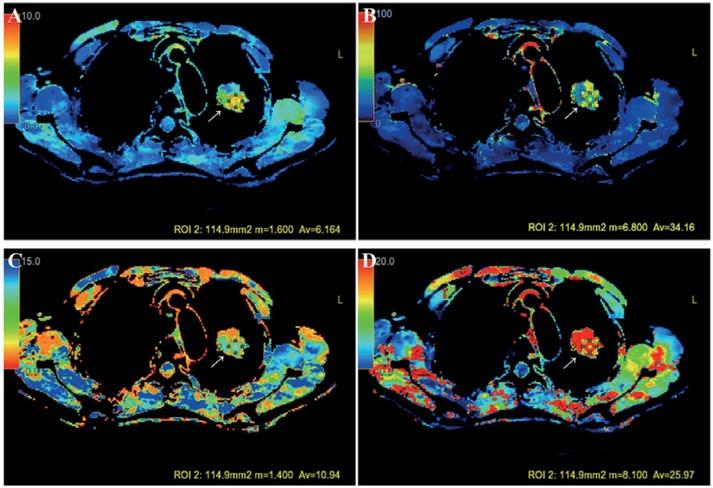

Figure 2